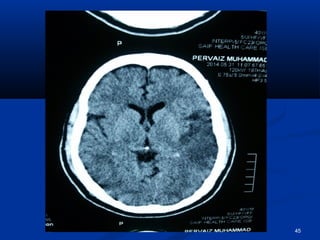

CCTT..bbrraaiinn

45

 HHee hhaasslleeuuccooccyyttoossiiss,,  RRaaiisseedd CCRRPP  RRaaiisseedd LLDDHH  UURRIINNEE :: nneepphhrriittiicc ppiiccttuurree  PPlleeuurraall fflluuiidd:: ttrraannssuuddaattiivvee.. (( ttrraannssiieenntt))  BBlloooodd ccuullttuurree :: - vvee  HHCCVV:: ++vvee .. AAuuttooiimmmmuunnee sseerroollooggyy :: -vvee..  AAnnggiiooggrraapphhyy:: nnoorrmmaall  CCTT.. bbrraaiinn,, EECCHHOO,, aanndd DDoopppplleerr II sshhoowweedd yyoouu.. 50